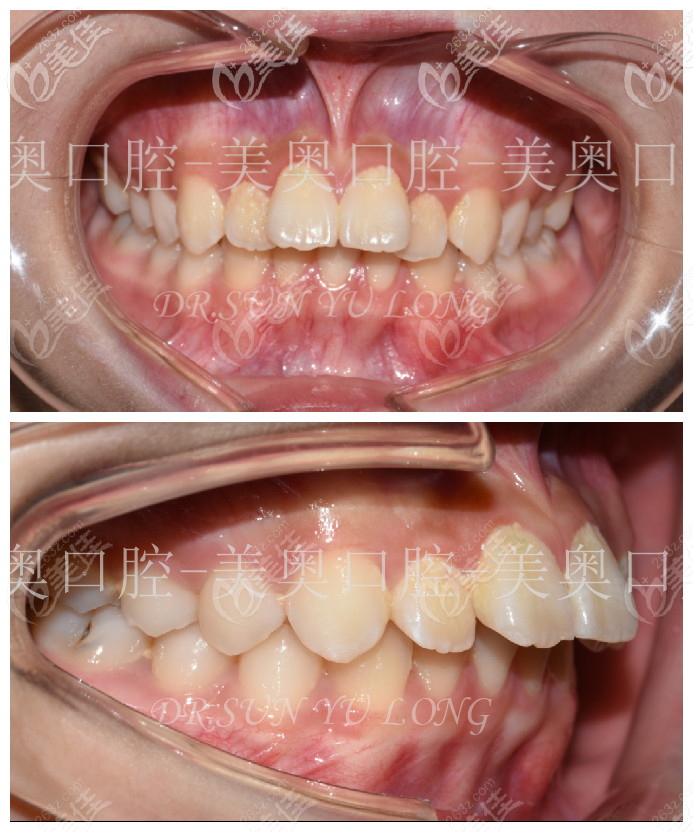

13岁的小豪替牙期出现牙齿前突,影响美观

牙列情况:拥挤

口腔卫生状况:一般

牙周状况:一般

口腔黏膜状况:无异常

咬合状况:

前牙覆合:正常

前牙覆盖:二度

中线:上颌正

下颌无

牙弓状况:

上牙弓:尖圆形,一度拥挤约2mm,11、21前突;

下牙弓:卵圆形,一度拥挤约1mm,31、32、42扭转,41先天缺失;

矫治8个月后现阶段小豪的牙齿看上去真的是改变了很多,整个人也变得乐观不少。